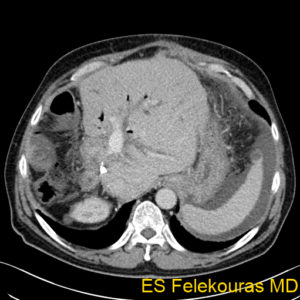

Τα ήπαρ ένα όργανο με πολλές λειτουργίες και έχει διάφορα νοσήματα και αρκετά από αυτά ιώνται με την Χειρουργική του ήπατος. Η συνηθέστερη επέμβαση που γίνεται στο συκώτι (ήπαρ) είναι η ηπατεκτομή (αφαίρεση ενός τμήματος του ήπατος) (εικόνα 1). Η πιο χαρακτηριστική ένδειξη για ηπατεκτομή είναι ένας κακοήθης όγκος. Όγκοι του ήπατος μπορεί να είναι πρωτοπαθείς (που αναπτύχθηκαν στο ήπαρ) ή μεταστατικοί (αναπτύσσονται σε άλλο όργανο, και κατόπιν μετανάστευσαν (μεθίστανται) στο ήπαρ). Ο πιο συχνός πρωτοπαθής κακοήθης όγκος του ήπατος είναι το ηπατοκυτταρικό καρκίνωμα (ηπάτωμα η ΗΚΚ), και μετά το χολαγγειοκαρκίνωμα (CCA). Η πλειοψηφία των ηπατικών μεταστάσεων έρχονται από το παχύ έντερο (mCRC). Γενικά η επιβίωση των ασθενών με κακοήθεις όγκους του ήπατος έχει βελτιωθεί τα τελευταία 20 χρόνια και στην πατρίδα μας, και εάν ο όγκος είναι ένας (μονήρης) ή περισσότεροι από ένα όγκοι αλλά περιορίζονται είτε στην αριστερά είτε στην δεξιά πλευρά του ήπατος μπορεί με την ηπατεκτομή να εχουμε 5-ετή επιβίωση που φθάνει και το 60%.

Μια ηπατεκτομή διαρκεί περίπου 3-5 ώρες και μπορεί να γίνει χωρίς την ανάγκη για μετάγγιση αίματος. Μέχρι 75% του ήπατος μπορεί να αφαιρεθεί χωρίς μεγάλους κινδύνους. Η παραμονή στο νοσοκομείο είναι περίπου 5-10 ημέρες και η πλήρης αποκατάσταση έρχεται σε 5-6 εβδομάδες. Το ήπαρ ξαναπαίρνει το μέγεθος του (σε μη κιρρωτικούς ασθενείς) σε 6-8 εβδομάδες. (εικόνα 2).